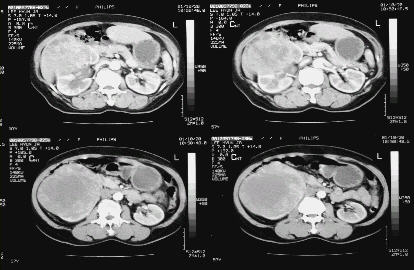

전산화단층촬영은 신종물의 평가에 초음파검사나 배설성요로조영술보다 정확하며, 신혈관 주위(신문부), 신장 주변, 신정맥, 하대정맥, 부신, 국소림프절 및 주위 장기로의 침윤 여부를 파악할 수 있어 신세포암의 병기를 결정하고 치료 계획을 세우는데 가장 중요한 검사입니다.

○ 복부전산화단층촬영(CT scan)

신종물의 평가에 가장 중요한 검사로, 혈관, 국소림프절 및 주위장기 전이유무를 판단하여 임상적 병기 결정하게 됩니다.

그림 3. 큰 우측 신세포암의 전산화단층촬영사진